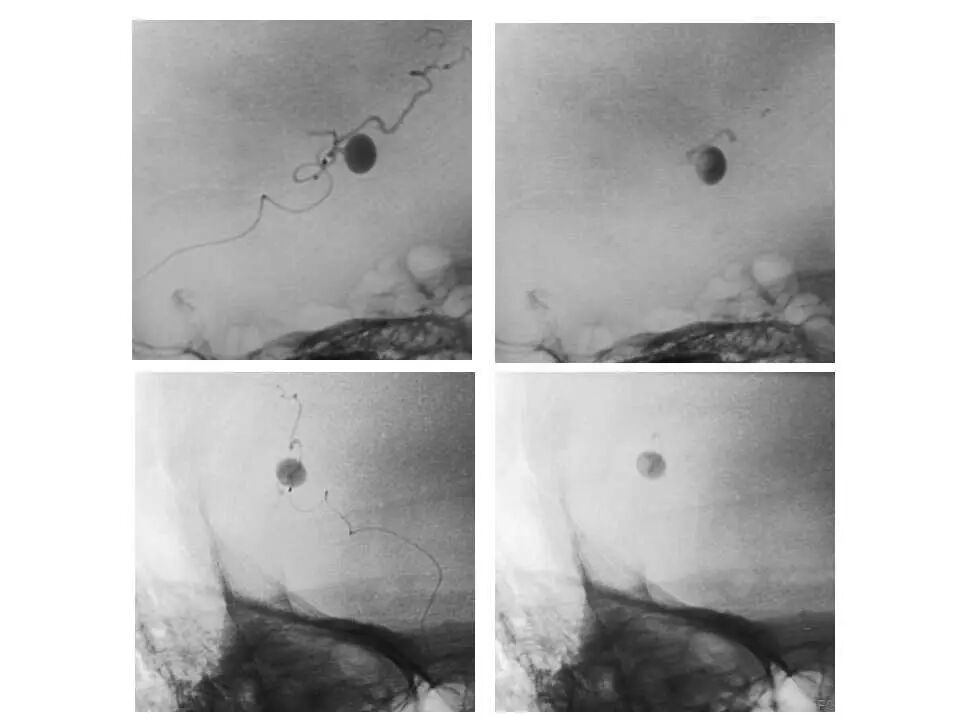

今天为大家分享的是“强生医疗CNV-神经介入专栏”第十五期,由首都医科大学宣武医院何川教授带来的“颅内动脉瘤介入治疗”精彩讲课视频及PPT,欢迎观看、阅读。文章仅代表作者个人观点,如有不同见解,欢迎同道斧正!

何川 ,首都医科大学宣武医院副主任医师,中国医师协会神经介入专业委员会常务委员,长期从事脑血管病和脊髓血管病的手术及介入治疗和相关研究工作。首都医科大学神经外科博士,师从于中国神经介入开创人凌锋教授;日本东北大学医院脑血管病治疗科博士后,师从于日本国脑血管病血管内治疗的开创者高桥教授。